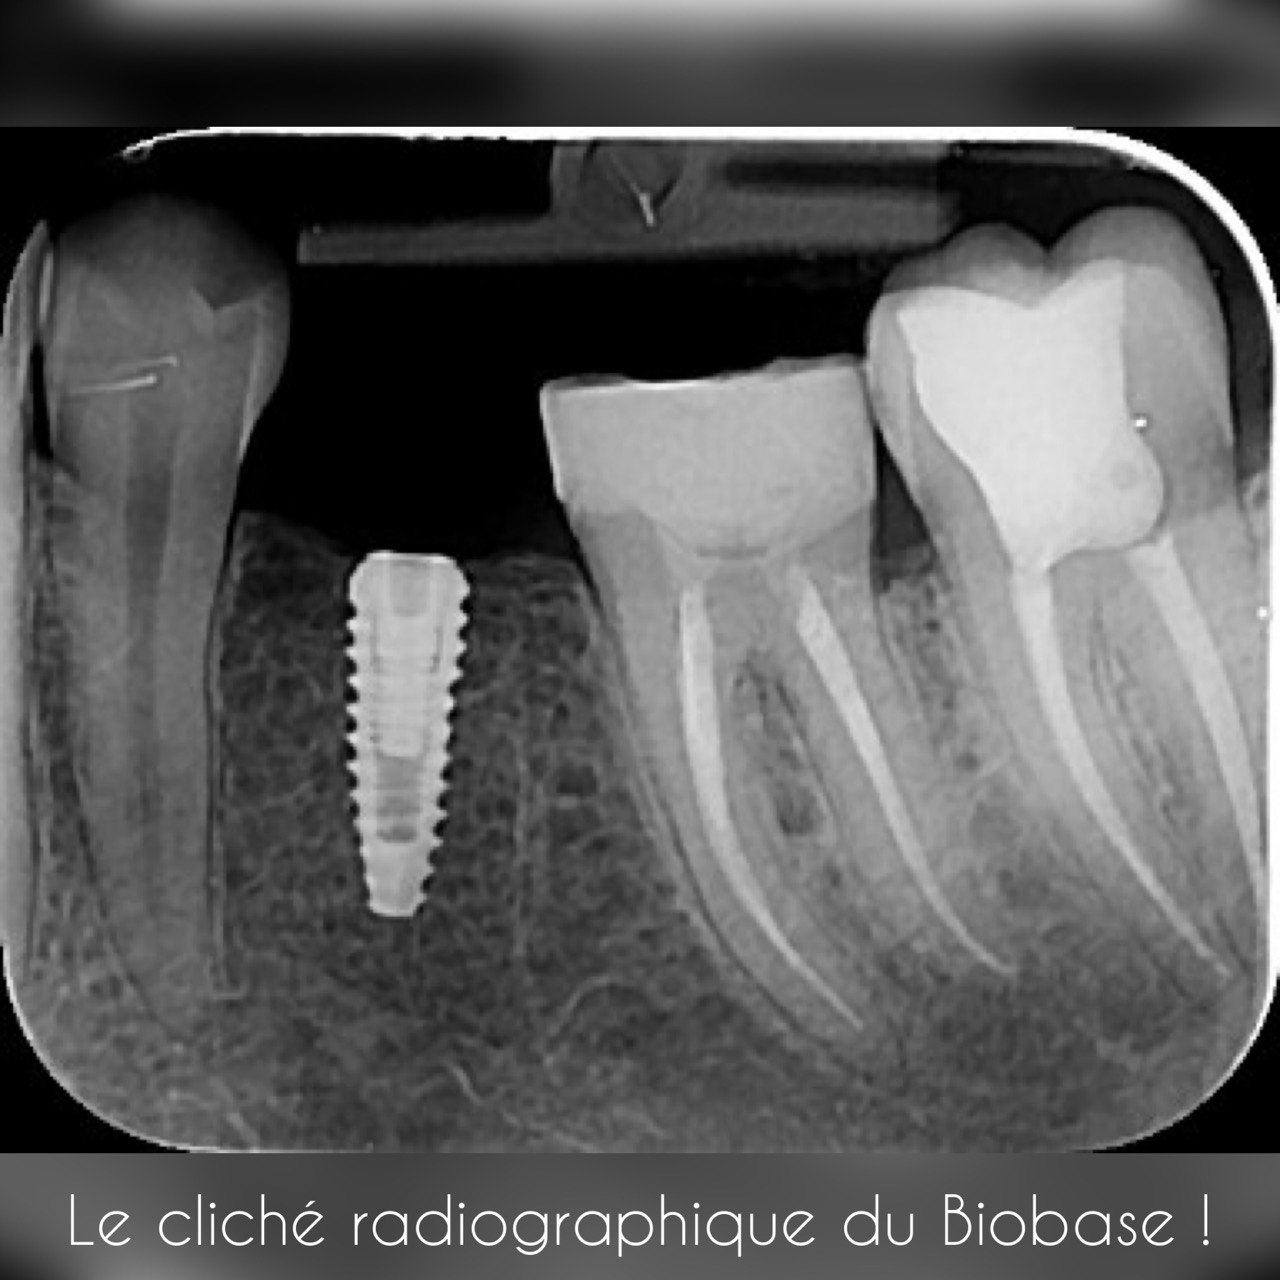

4. What option can be selected regarding the implant seen in this X ray?